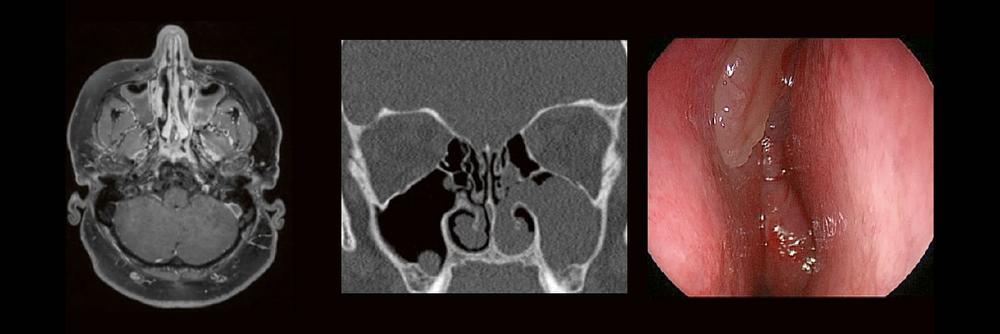

HNO & Radiologie: gemeinsam durch die NNH – ein Joint Venture (Webinar | Online)

Dr. med. André ReisbergDr. med Sebastian Plößl Die bildgebende HNO-Diagnostik macht es Anfängern nicht leicht. Die Anatomie ist komplex und weniger intuitiv als in anderen Körperregionen. Normvarianten erschweren insbesondere in den Nasennebenhöhlen den Lernprozess. Sobald pathophysiologische Zusammenhänge verstanden und wichtige klinische Aspekte verinnerlicht wurden, gelingt es einen praxistauglichen, belastbaren Befund zu erstellen. Wo muss ich eigentlich hinschauen? Was will der Kliniker von mir wissen und warum? Begleiten Sie uns auf einer kooperativen Reise durch die NNH mit „Ach so!“-Garantie: Gemeinsam mit einem HNO-Chirurgen werfen wir einen Blick IN die NNH – mal in grau, mal in Farbe. Denn alles fällt leichter, sobald man verstanden hat, warum man es tut. KOSTENFREIDie Teilnahme am RADCAMPUS ist…